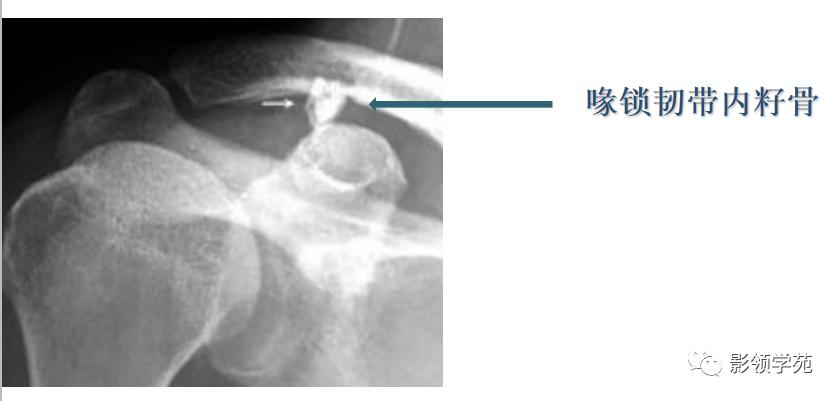

籽骨是由肌腱骨化而成,有改变压力消除肌腱与骨面之间的摩擦、变换肌的牵引力方向加大肌及稳定关节的作用。

永存骨骺、籽骨和副骨的发生与其特有部位及典型特征紧密联系。

常见案例均具有骨块边缘钝圆、骨皮质连续、局部软组织无明显肿胀以及伤后该骨的连续摄片无明显变化等非撕脱性骨折的共同特点。

籽骨、副骨与永存骨骺一般边缘光滑, 周围皮质密度较高, 皮质光整, 附近骨质结构完整, 具有对称性, X线随诊形态及位置不会发生改变, 一般不会引起疼痛。但个别患者由于一些局部肌肉的扭伤而引起副骨的移位, 或由于机械外力的作用使副骨摩擦软组织导致滑囊炎和肌腱炎, 甚至由于长期慢性磨损可与附近正常骨质形成假关节从而产生创伤性关节炎可引起疼痛。而骨折一般具有明确的外伤史, 附近软组织肿胀明显, 疼痛症状明显, 断端锐利, 皮质断裂, 不具有对称性, X 线随诊形态及位置可发生移位。而籽骨、副骨与永存骨骺本身也可在外伤的情况下发生骨折, 但极罕见。